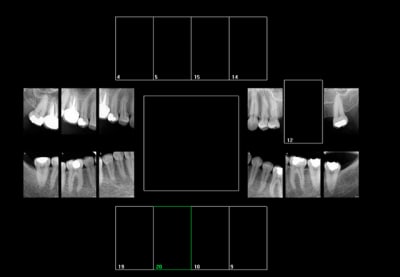

Comment cotez vous ces clichés ?

HBQK191 (16, 14)

Dents contiguës de 16 : 17,15

Dents contigues de 14 : 15, 13

2 secteurs distincts ? ou pas assez centré sur 16 ( qui est tout aussi centrée que 15) ? -)))))

Allez y vos cotations pour ces radios. Pas de signes d'appels.

Attention aux notions de dent "centrée" et celle de secteur de 3 dents contigues.

Côté droit, aucun doute possible : tu n'as droit qu'à 3 Clichés, on va dire 18 15 12..., mais ça peut être 46 15 12..., voire 17 44 13..., ou encore 17 45 12..., ça passe aussi.

Côté gauche, c'est plus discutable : je dirais que je prends 4 clichés, maintenant c'est le n° des dents qui pose problème..., on va dire 24 28 35 37..., mais sans conviction...

coté droit : 12 17 (ou 16) 44 46 ( pas contigue de 17 il me semble lol !, meme si elle est sur la meme rétro coronaire) et possibilité d'atteinte pulpaire vu la bouse d'amalgame qui justifie la rétro alvéolaire)

Gauche : 25 ( rétro alvéolaire là aussi suspicion d'atteinte pulpaire vu la bouse de composite en vestibulaire) 28 34 37.